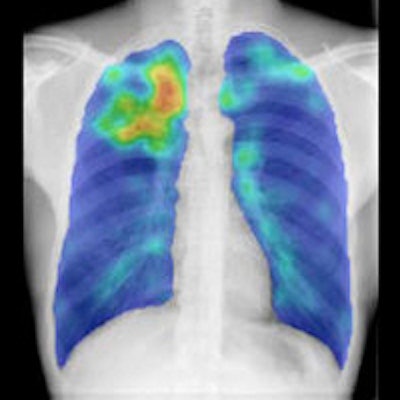

Editor's note: The image on the home page that introduces this topic shows that the application of energy normalization improved CAD's ability to distinguish normal from abnormal chest radiographs. It was courtesy of Dr. Rick Philipsen from Radboud University Medical Center.